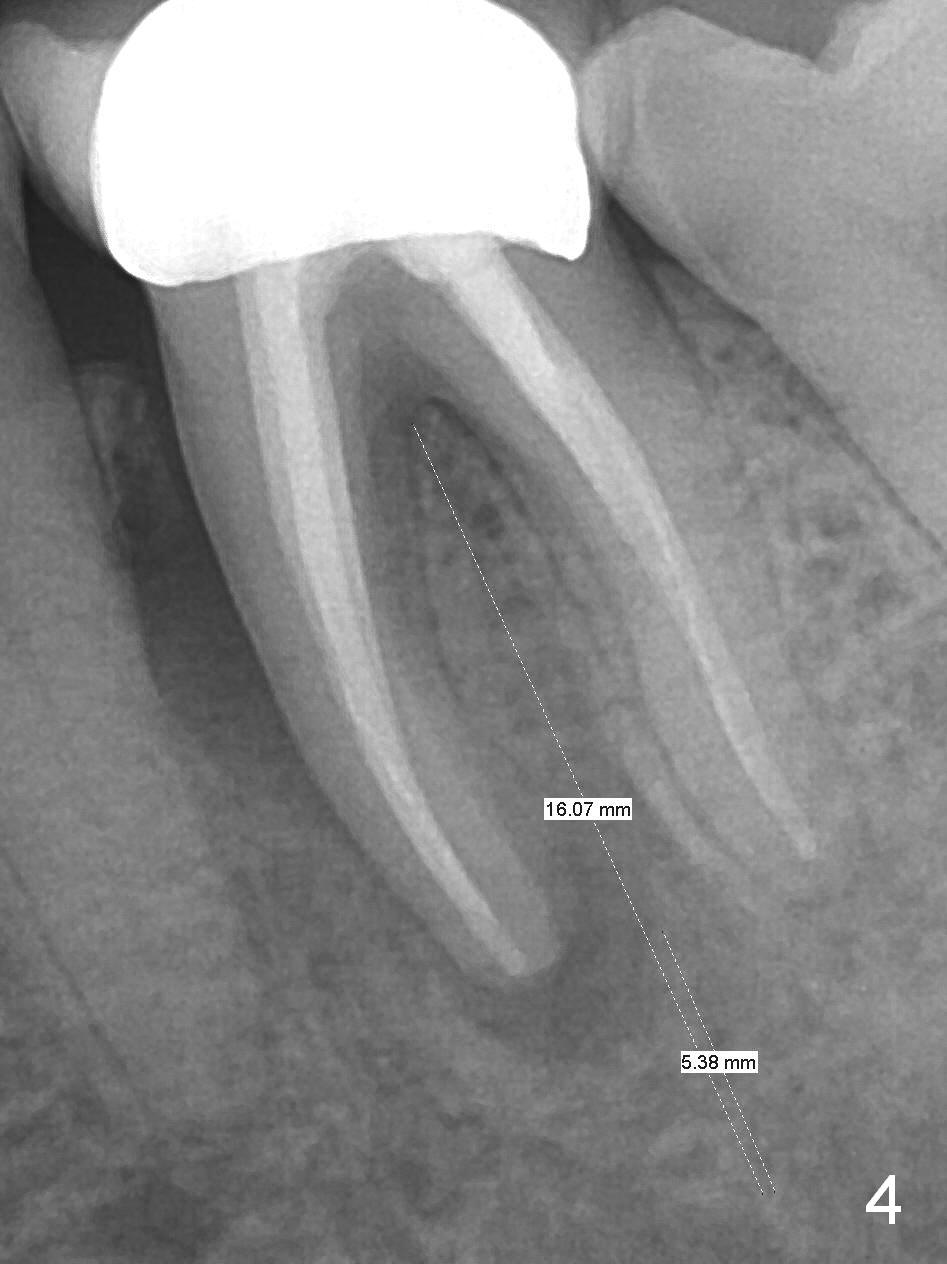

A 59-year-old woman had root canal therapy for the tooth #19 10.5 years ago (Fig.1 (red dashed line: the superior border of the Inferior Alveolar Canal). Two years later there was apparent periapical radiolucency with the distal root (Fig.2 *). The tooth remains asymptomatic until the last six months. There are 2 fistulae associated with the tooth: mesiolingual and buccal furca. Radiogra-phically, there are 2 radiolucent lesions: mesial and apical to the mesial root (Fig.3 *). If a 16 mm implant is placed, there will be approximately 5 mm apical bone (Fig.4); 7 mm for a 18 mm implant. The bone height is 25 mm (Fig.6). Therefore, once initial osteotomy is established with a 13 mm long drill with PA confirmation, the osteotomy is extended to its depth with 1.5x21 mm drill (Fig.5). After socket treatment with Metronidazole gauze with Epinephrine (1: 50,0000), take PVS impression of the socket to catch the large mesial defect. A fair amount of allograft and Osteogen is expected. It has been 9 months since last visit. Retake PA before surgery. If the mesial defect enlarges, start osteotomy in the distal slope of the septum.